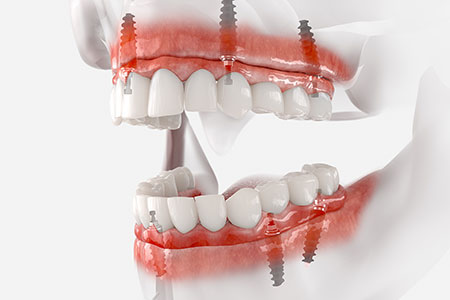

すべての歯を失った、総入れ歯が合わずにお悩みの方へ、従来は8~14本のインプラントが必要でしたが、オールオン4なら最小4本のインプラントで12本の噛める歯をしっかり支えられます。

骨の硬い部分を正確に狙い、角度や力を調整してインプラントを埋入。器具の長さや太さも最適化し、安定した咬合を実現します。オールオン4は高度な技術が必要なため、対応できる歯科医師や医院は限られています。

オールオン4とはたった4本のインプラントで12本の歯を保持する方法です。全ての歯を失ってしまった方、総入れ歯の方に行う治療法です。抜歯からインプラントの埋入、仮歯を入れるまでが1日でできます。

通常のインプラント治療は、部分的な歯の欠損を補う治療法が一般的です。顎の骨にインプラントを埋入し、骨としっかり結合するのを待って上部構造(被せ物)を装着します。オールオン4はこの治療法の応用編と言えるでしょう。